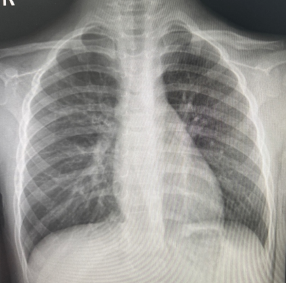

朱某,男,2016-3-15出生,因“跌倒致左肩疼痛伴活動受限2小時”2019年12月12日來我院門診。檢查發現左鎖骨區見腫脹、畸形,明顯壓痛,左肩活動受限。本院X線攝片示:左鎖骨骨折,斷端明顯重疊移位(圖1),予以8字繃帶外固定制動,定期隨訪。2020年1月17日復診述左肩無腫痛,活動基本正常,攝片示:左鎖骨骨折,斷端對線欠佳,局部明顯骨痂形成(圖2)。2020年6月8日再次復查攝片示:左鎖骨骨折,斷端對線可,已骨性愈合(圖3)。2023年9月26日再復查攝片示:左鎖骨骨折部位已完成塑形,與健側無明顯差異(圖4)。

圖2 明顯見骨痂形成